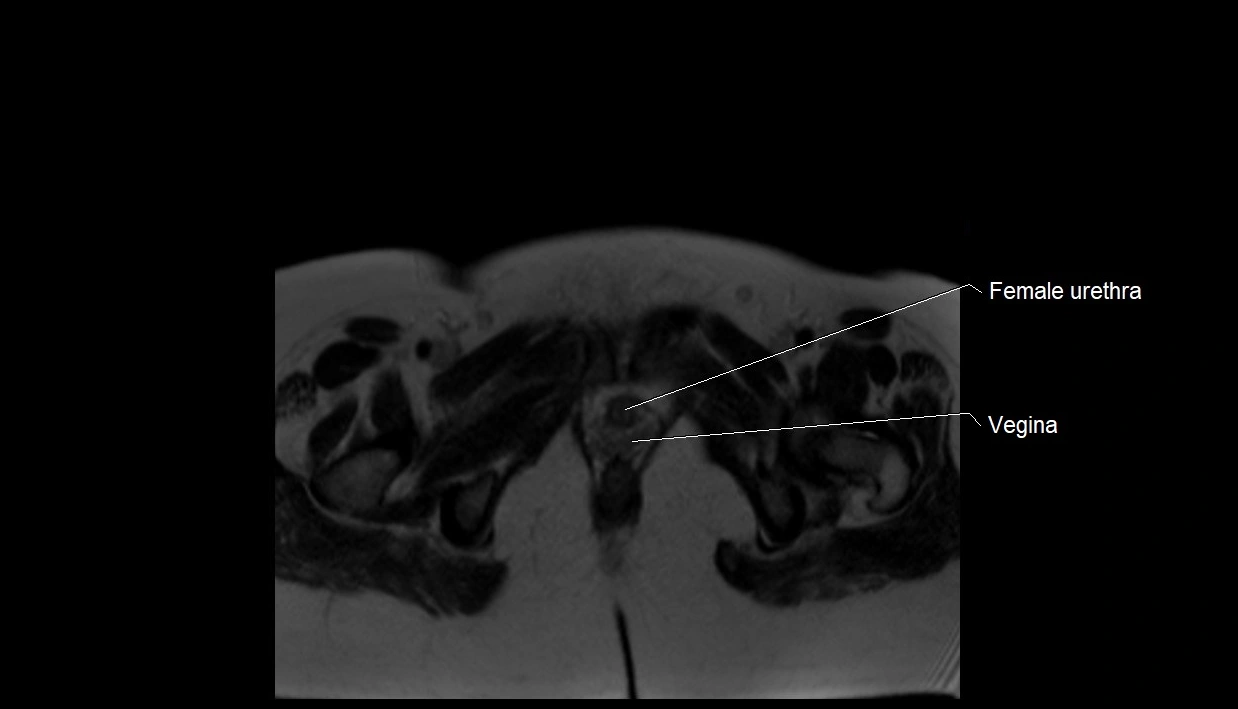

MRI image

image